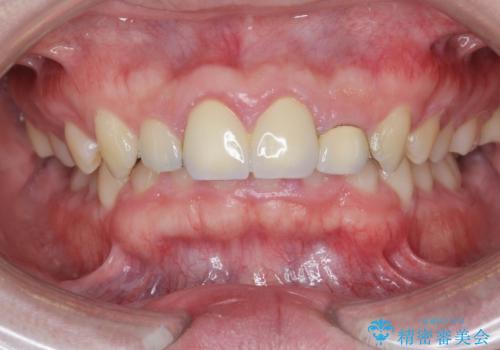

歯周外科を行い、歯ぐきの状態を整えた前歯セラミック治療

- 「前歯の見た目、歯ぐきの腫れを改善したい。」と希望され来院されました。

前歯には接着性の維持装置や、中途半端な形の連結クラウンが装着され、清掃性が悪く歯ぐきの腫れや、歯ぐきの形態の不揃いが認められました。

歯周外科を行ったことで、歯ぐきの形態や腫れが改善され、審美性だけでなく清掃性も大きく改善することができました。